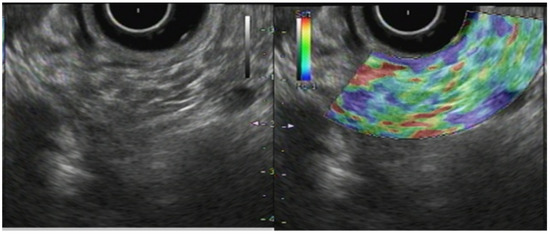

Ohno et al. described EUS-SWE effectiveness for assessing autoimmune pancreatitis (AIP) [12]. They found the median vs. to be significantly higher in patients with AIP (2.57 m/s) than in normal controls (1.89 m/s). Furthermore, mean vs. was found to be significantly lower in the former group after steroid treatment. These were measured as more sensitive indicators than changes in pancreatic parenchyma size or serum lgG4 levels after two weeks of treatment. These results provide new insights into pancreatic hardness, where it is high during active inflammation in AIP and decreased upon steroid therapy. Moreover, Dietrich et al. reported that pancreatic hardness might remain high after steroid treatment in AIP with a high risk of relapse. That hardness was implicated as an indicator for relapse assessment [30]. Furthermore, after they evaluated the utility of elastography for diagnosing AIP, they reported characteristic elastography patterns at the site of AIP masses and in the surrounding pancreatic tissue. Taken together, these reports support the use of EUS-EG for evaluating inflammatory activity in pancreatic inflammatory diseases such as AIP, although the study of more cases is necessary.